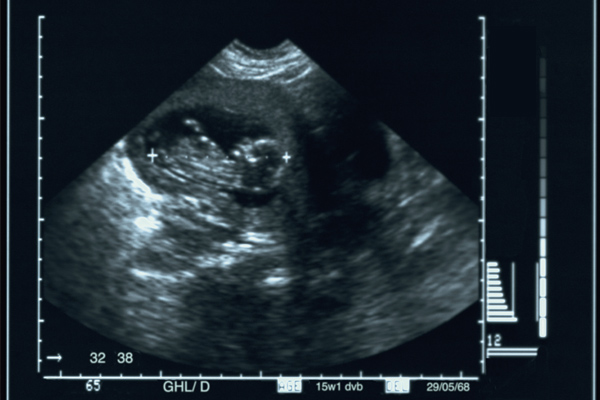

O Governo do Estado, por meio da Secretaria de Estado da Saúde, está entregando aparelhos de ultrassom para sete hospitais da rede estadual, possibilitando a ampliação do atendimento nos municípios de Pombal, Monteiro, Queimadas, Guarabira, Itaporanga, Picuí, Catolé do Rocha e regiões circunvizinhas. A tecnologia do aparelho de ultrassom permite o diagnóstico por imagem de forma segura e não invasiva em pacientes adulto, pediátrico e neonatal, para o diagnóstico de agravos em diversas áreas da medicina.

O tipo de aparelho em questão será destinado para diagnósticos ginecológicos, obstétricos, vasculares, cardiológicos, abdominais, de pequenas partes (mama, tireóide, testículos, etc), abdominais, urológicas e musculoesqueléticas com base de rodízios. Para a diretora do Hospital Regional de Catolé do Rocha, Thais Medeiros, muitas pessoas só têm acesso a este tipo de exame por meio do serviço público. “Para nós do Hospital de Catolé do Rocha, o equipamento chega num excelente momento, especialmente porque damos suporte a cerca de dez municípios vizinhos, o que corresponde a uma média de 110 mil pacientes atendidos por ano”, pontuou